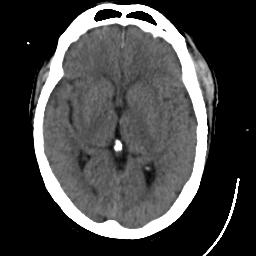

Meningioma: Roentgen-ray CT #1 -- Slice #10

[Home][Help][Clinical] Slice 10